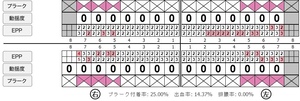

歯周病検査(治療前)

歯周病検査(治療後)

| 担当者所見 | あまり器用な方ではなかったため、決まったところがいつも磨けず奥歯に歯間ブラシがなかなか入れられませんでしたが、歯間ブラシのサイズを変えてみたり、内側から入れてみたりと試行錯誤してなんとかある程度磨けるようになりました。 その結果、出血が100%から7%へ激減することができました。 ただSRPをしただけではここまでの結果は出なかったと思います。 それほど日々のセルフケアが重要だということを再認識しました。 歯周ポケットが残っている部位、出血がある部位に関しては引き続き歯磨きを念入りに行なってもらう。 |

| 担当者所見 | 全体的に出血が見られたのと、奥の歯ぐきは炎症があり歯周ポケットが深かった為、まずは歯ブラシの当て方+歯間ブラシ3Sサイズを使用して頂き炎症を落ち着かせました。 両方毎日使用して頂いた為、スムーズに歯周病治療を行うことができました。毎日のホームケアが不十分だと、なかなか結果に繋がらず、治療期間も長くかかってしまう為、患者様の協力が歯周病治療を成功させるためにはかなり重要になっていきます。 そして一度病気になった歯ぐきは再発しやすい為、今後は3ヶ月に1度の定期的なメインテナンスで、この状態を維持できるよう一緒に管理していきます。 |